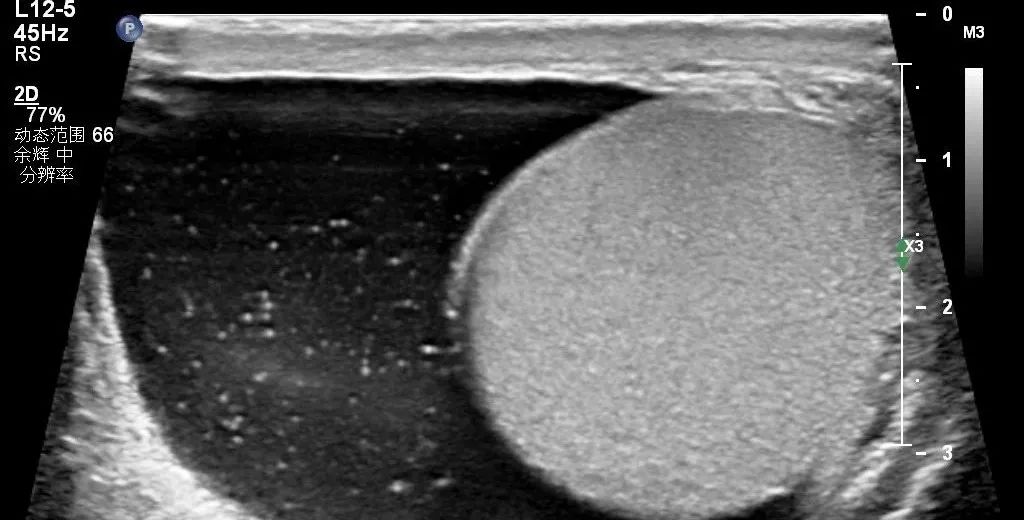

①睾丸鞘膜积液——鞘状突闭合正常:既然是睾丸鞘膜积液,那积液就是出现在睾丸周围的鞘膜腔内,也可以说积液位于阴囊内,并不向精索或腹股沟区延伸(图1)。此时若积液量较多,其声像图特征表现为睾丸「背靠陆地、三面环海」,类似半岛。

图1示意图显示积液量较多时的睾丸鞘膜积液

超声表现为:阴囊无痛性肿大,大量积液时睾丸附睾触诊不清。

睾丸鞘膜积液:积液三面包绕睾丸周围